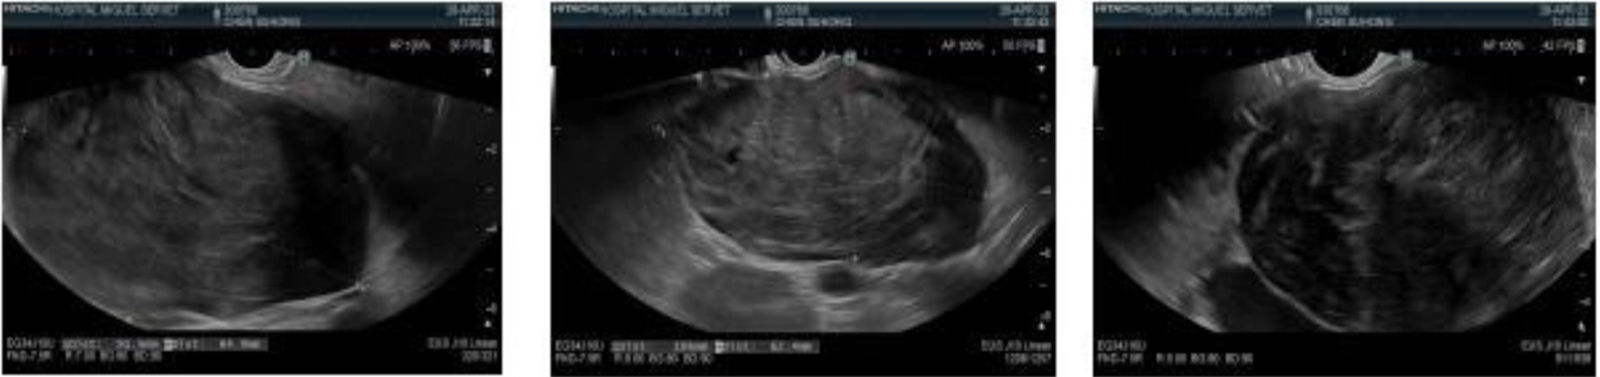

Echoendoscopy (Fig. 2) identified an exophytic, hypoechoic, well-delineated subepithelial lesion dependent on the muscle layer of the duodenal wall, measuring approximately 10 × 7 cm, that was highly suspected to be a gastrointestinal stromal tumor (GIST). A fine-needle puncture (FNP) was performed and immunohistochemistry revealed diffuse, intense positivity for desmin and caldesmon, the absence of typical GIST markers (CD117, DOG-1), and negative CD34, S100, and CKAE1-AE3. The mitotic index of 3–4 mitosis/mm² and high Ki-67 reinforced the suspicion of a smooth muscle tumor.